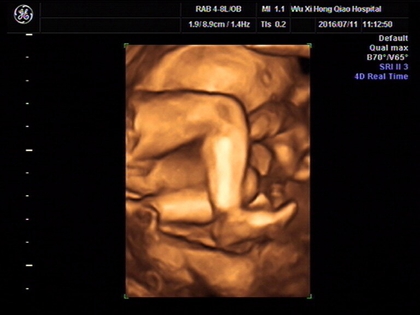

网上有一种说法是,在做四维彩超的时候,如果是女宝宝是比较不容易配合的,如果是男宝宝更容易通过,那么是不是四维女宝更容易配合呢,四维女宝特征有哪些?更多关于生男生女的相关内容尽在孕宝网。

四维女宝宝特征有哪些?